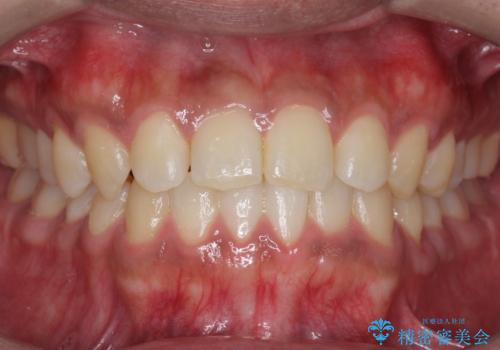

【非抜歯】インビザラインで正しい噛み合わせを

【非抜歯】インビザラインでガタつきと口元を改善!非抜歯でも印象が変わる矯正治療